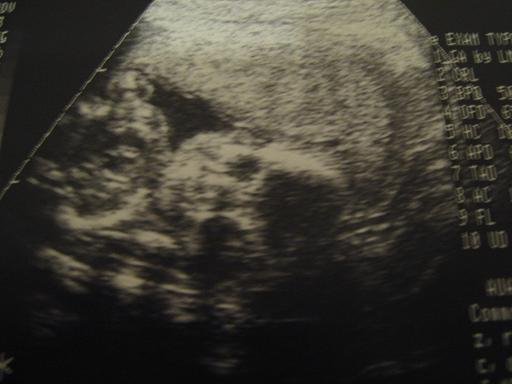

És képek 10.31-éről.